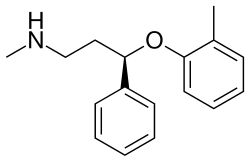

Selective norepinephrine reuptake inhibitors

Serotonin–norepinephrine reuptake inhibitors (SNRIs)